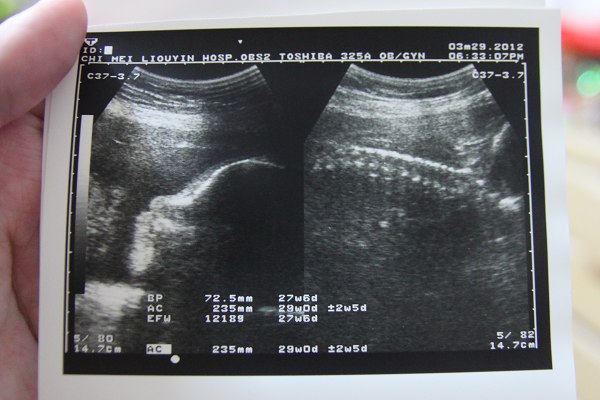

2012.03.29 (29W)

因為已經確定要剖腹

雖然還沒看日子

但也確定是倒數十週了

啊啊小妞妞成長也在正常範圍內

本月體重還是增加一公斤~來到77kg了

血糖測試果然過高

不過醫生允許我不用複檢(好SWEET)

只是要我小心醣類攝取